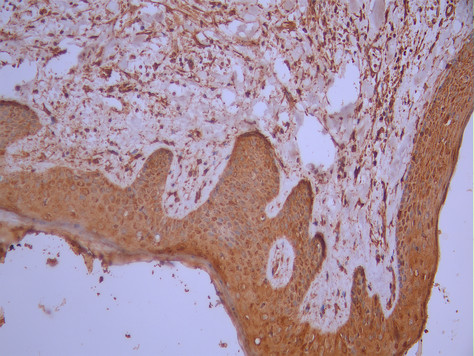

IHC image of CSB-RA699080A0HU diluted at 1:100 and staining in paraffin-embedded human skin tissue performed on a Leica BondTM system. After dewaxing and hydration, antigen retrieval was mediated by high pressure in a citrate buffer (pH 6.0). Section was blocked with 10% normal goat serum 30min at RT. Then primary antibody (1% BSA) was incubated at 4°C overnight. The primary is detected by a Goat anti-rabbit polymer IgG labeled by HRP and visualized using 0.05% DAB.